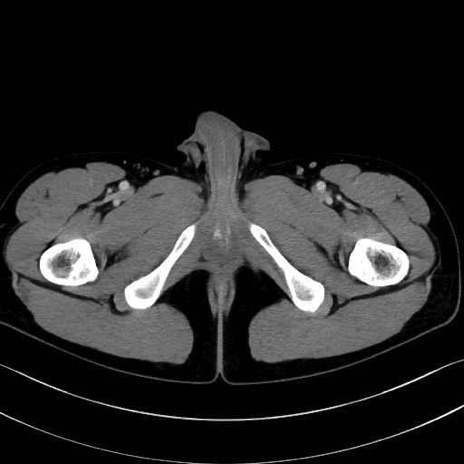

5. 大腿前面(大腿四頭筋群・伸筋群)

縫工筋 (Sartorius)

大腿直筋 (Rectus femoris)

外側広筋 (Vastus lateralis)

中間広筋 (Vastus intermedius)